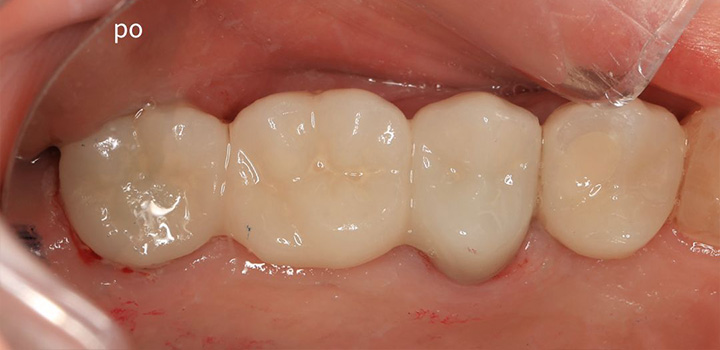

Efekty, które mówią same za siebie